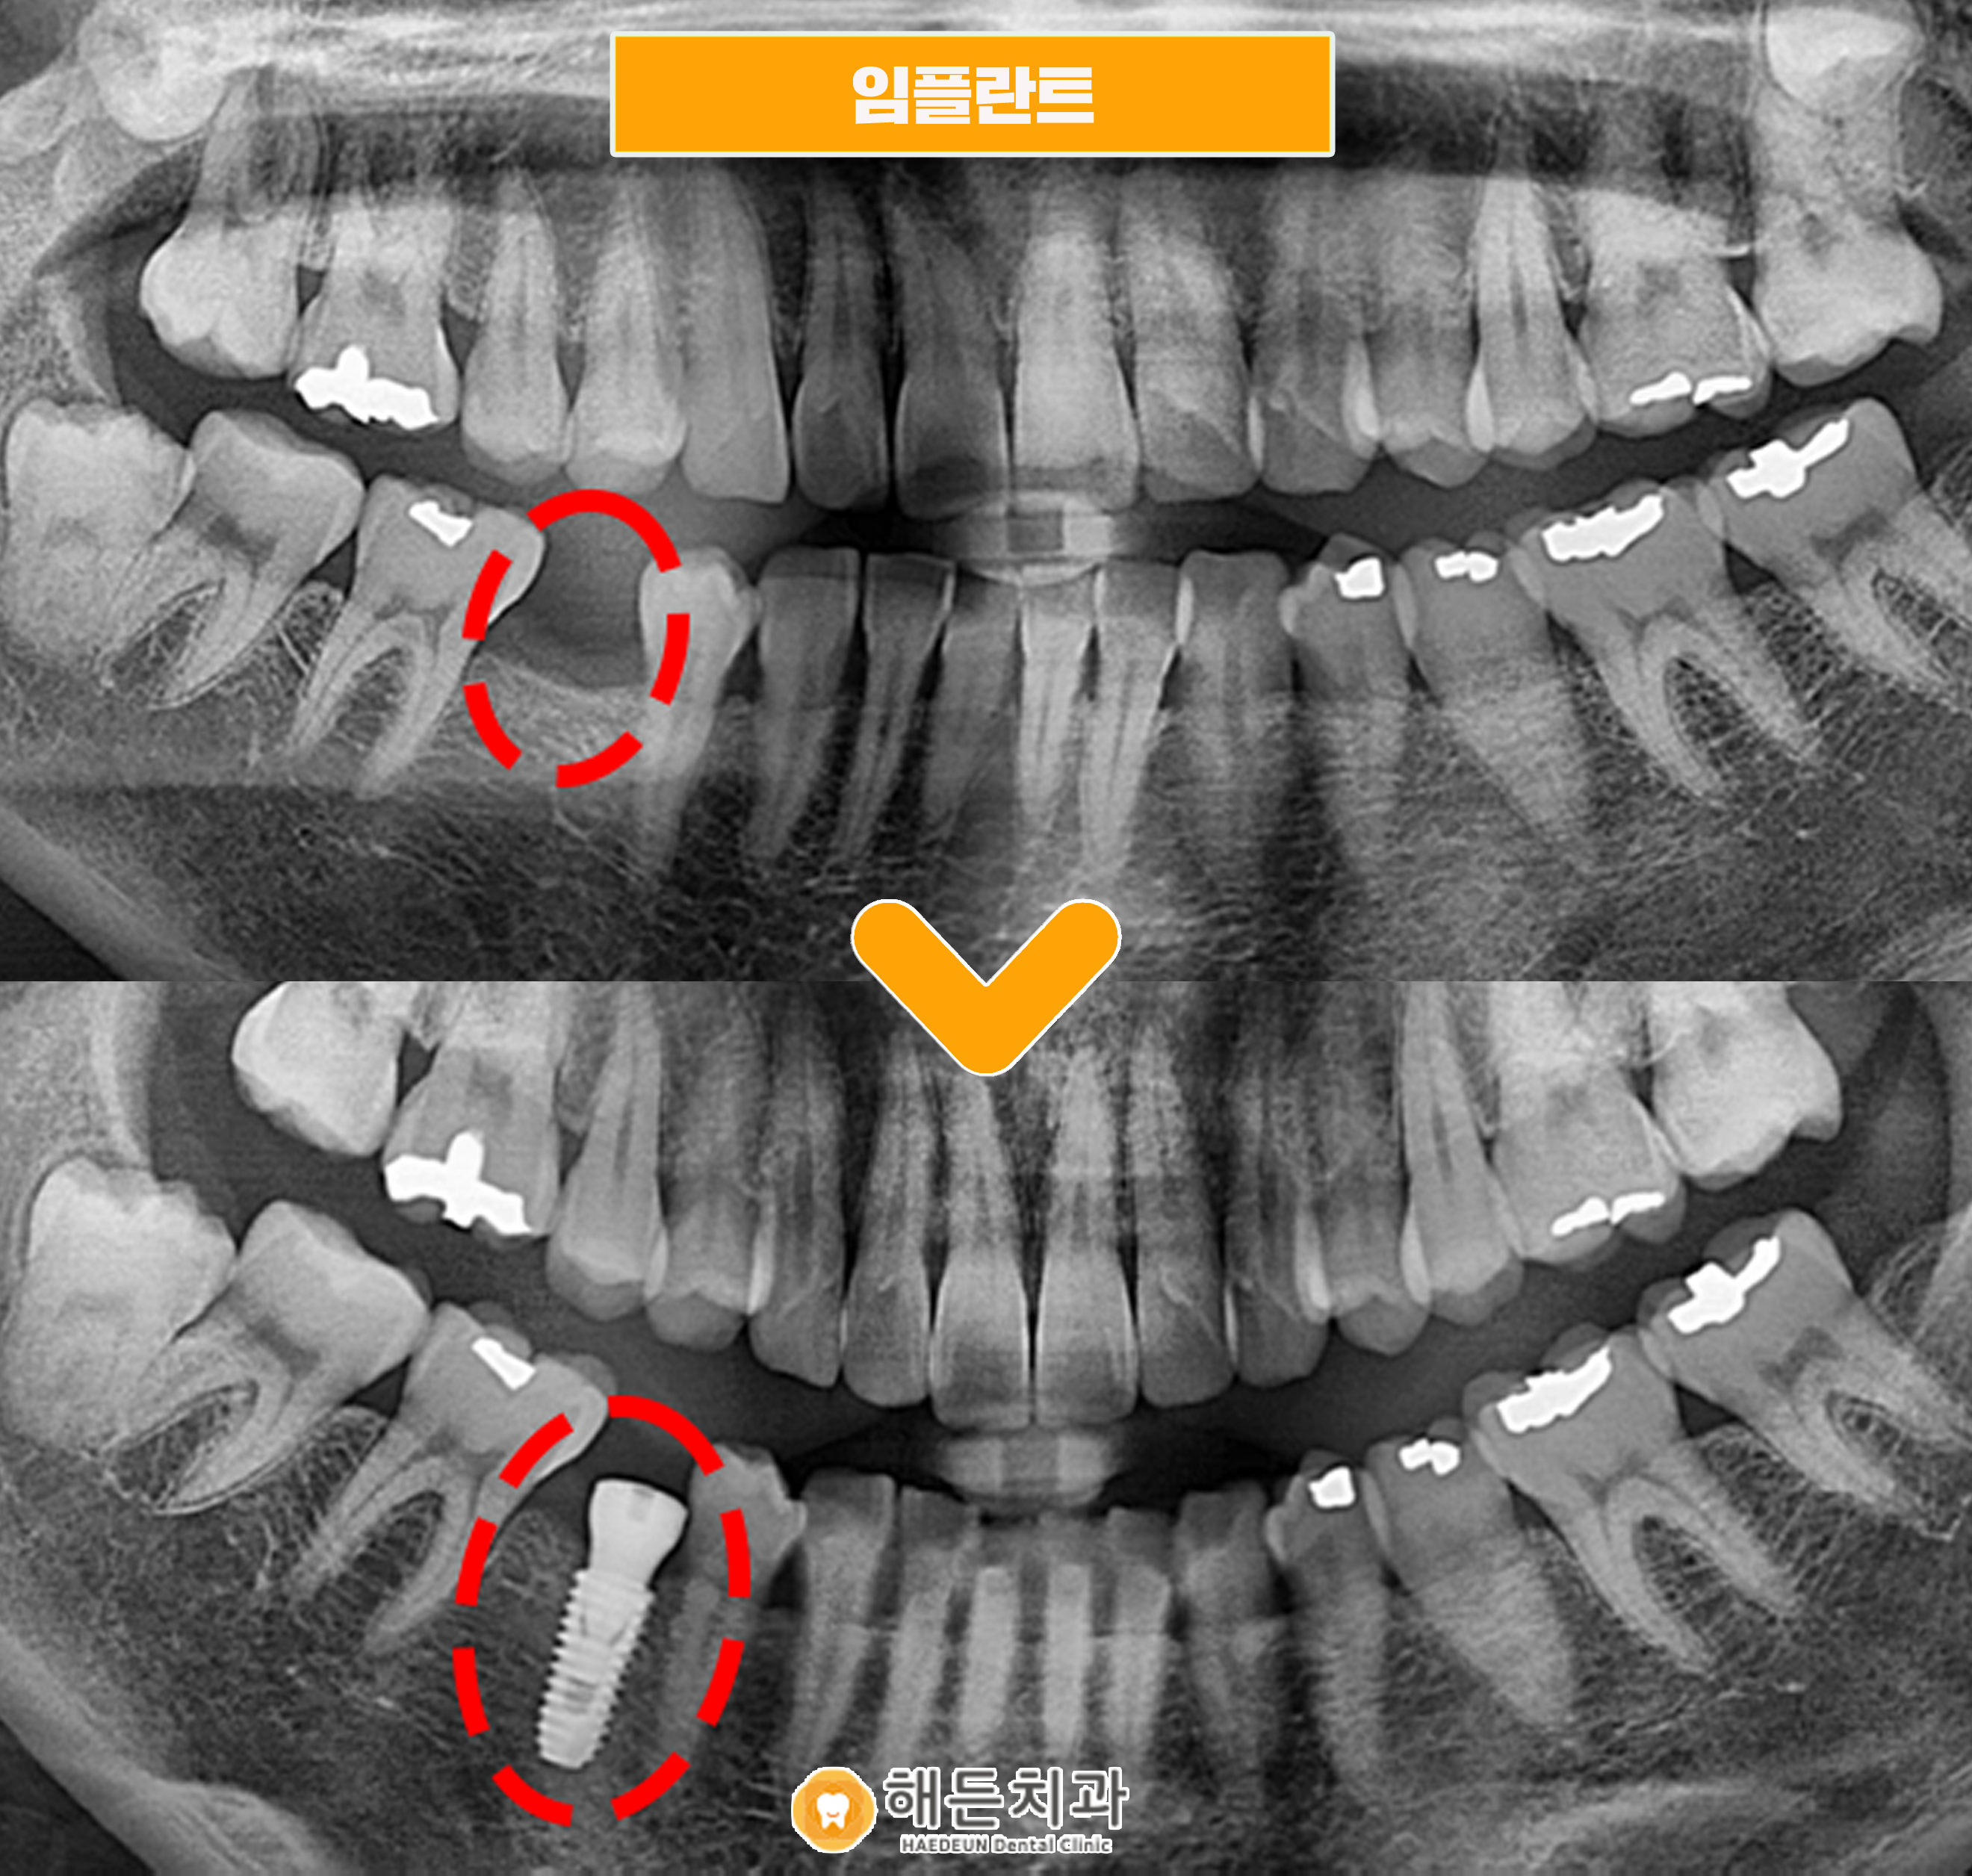

위 사진은 천안아산치과 해든치과에 내원하신 김*지님의 치아 사진입니다.

김*지님은 하악 오른쪽 부분 빨간색 표시한 부분, 작은 어금니 즉 소구치가

발치한지 10년 넘은 상태로 아이 낳고 처음 치과 오신 상태였습니다.

다행히 환자분께서는 뼈 상태 좋아서 뼈이식 없이 임플란트 식립이 가능했습니다.

파노라마 사진과 같이 식립 후 보철물 치료 전까지 치료를 한 상태입니다.

사진을 보시면 잇몸뼈와 임플란트가 잘 유착돼 있는 것을 확인할 수 있습니다.